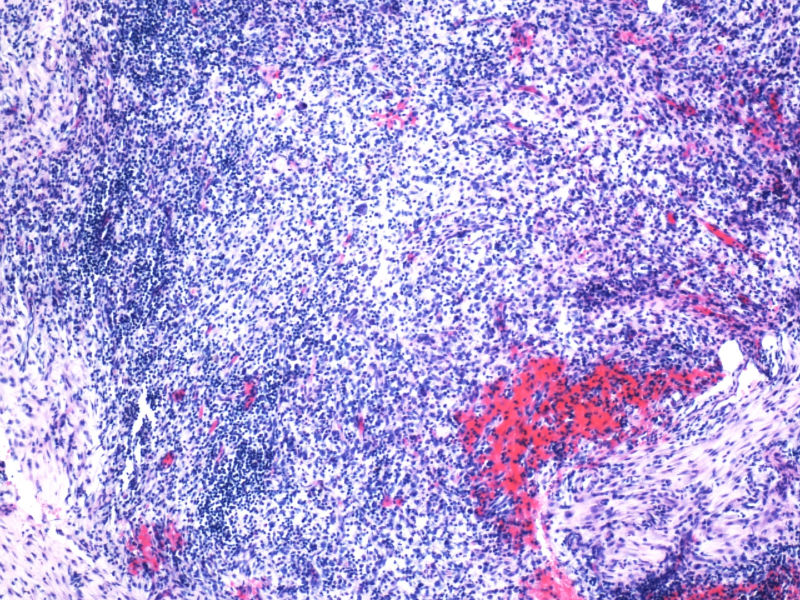

最终诊断为:ALK阳性的间变性大细胞淋巴瘤,淋巴组织细胞变异型。

拿出来的目的:本例始发于骨骼,临床提示脓肿或骨髓瘤,ALK阳性但EMA阴性,细胞毒只有一个标记阳性,本例CD4不阳性。因为CD30和CD15均有非肿瘤细胞阳性的情况,所以对于这个骨骼病例,细胞少而退变,因此最初没有信心诊断,但ALK一般不在非肿瘤细胞内阳性表达,所以最终还是诊断了ALCL。

此病例是非常特殊,其表现为:

1)ALCL很少原发于骨组织,

2)肿瘤细胞免疫表型特殊, CD30+CD15+ALK-1+CD43+Perforin+, 而其他PanB细胞和PanT细胞的标记均为阴性。

3)楼主诊断ALCL主要根据是 ALK-1+, 很有说服力!